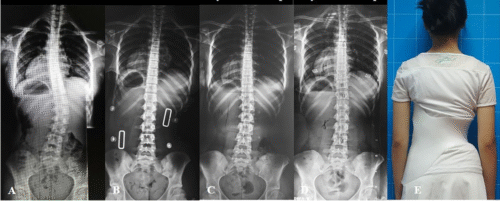

اعوجاج العمود الفقري أو الجنف هو انحناء غير طبيعي في العمود الفقري يجعله يميل إلى أحد الجانبين. قد يكون الانحناء بسيطًا ولا يسبب أعراضًا واضحة، وقد يتطور مع النمو ليؤثر على شكل الجسم، وضعية الكتفين، وحتى على القدرة على التنفس في بعض الحالات.

الكشف المبكر عن اعوجاج العمود الفقري يمنح فرصة أكبر للعلاج بدون جراحة. فالأطفال والمراهقون الذين يُكتشف لديهم الاعوجاج في مراحله الأولى يمكن السيطرة على حالتهم باستخدام العلاج الطبيعي، الأحزمة الطبية PioBrace، أو برامج علاجية متخصصة. أما في الكبار، فيساعد التشخيص المبكر على منع المضاعفات وتخفيف الألم.

ألم الظهر شائع جدًا ولا يعني بالضرورة وجود اعوجاج في العمود الفقري. لكن في بعض الحالات، قد يكون الألم إشارة مبكرة لوجود انحناء يحتاج إلى تقييم. التشخيص المبكر والمتابعة الطبية يقللان من المضاعفات، ويمنحان المريض فرصة لحياة أفضل بدون ألم.

الاعوجاج حالة مستمرة ولهذا السب قد تحتاج تدخلًا في مراحل مختلفة من العمر. وبفضل وجود تقنيات التصنيف المعتمدة ، يمكن للأطباء تصميم خطة علاجية مخصصة تضمن تدخلاً جراحيًا عند الضرورة أو العلاج غير الجراحي قبل ذلك، لتفادي الاضطراب في الوظائف التنفسية أو أي أعراض متأخرة. فريقنا المحترف يضم نخبة من الأطباء والمتخصصين الذين يجمعون بين الخبرة والاحترافية لتقديم خطة علاجية شاملة ومخصصة لحالتك، تضمن السيطرة على الانحناء ومنع زيادته.